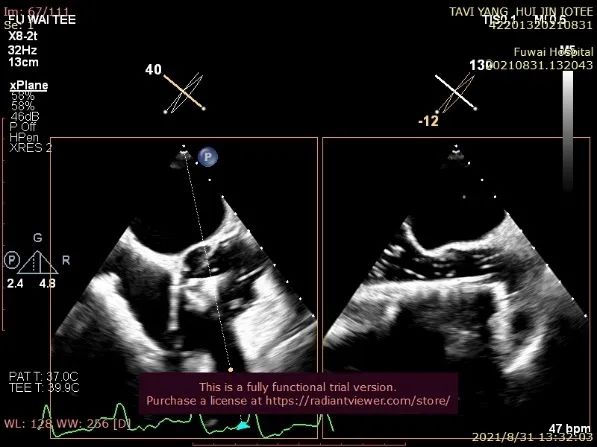

单弯管交换硬导丝后,用16F扩张鞘预扩心尖穿刺处,将 J-valve瓣膜(27号)装入输送器,将输送器推送至主动脉根部(通过零造影剂DSA确认),释放定位件,患者无需起搏,适当调整定位件角度使其进入三个主动脉窦部(图3)。

图3. TEE和放射线显示定位件入窦,人工瓣入座

通过TEE确定三个定位件准确入窦后完全释放瓣膜(图4),再次用TEE观察人工瓣膜自膨后金属支架的形态(自膨胀后最大外径)、位置(瓣环下金属支架长度及占比)、有无明显瓣周漏。撤出输送器(图5),收紧心尖处荷包线并打结,检查无出血,逐层关胸,封皮,拔出股动脉鞘并在股动脉穿刺处压迫止血。手术过程顺利,患者生命体征平稳。

图4. TEE和放射线显示人工瓣膜自膨